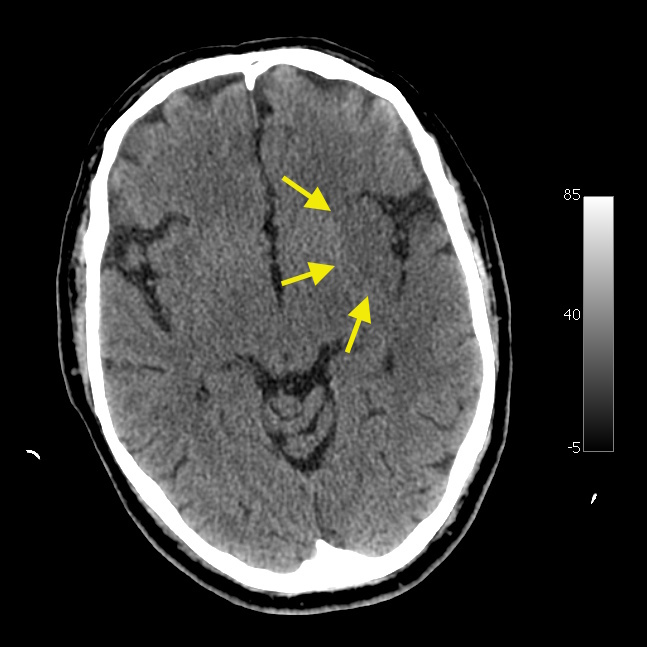

岛叶带征(岛带征)

正常情况下,岛叶皮层的灰质与白质界限清晰。当岛叶皮层发生急性脑梗死时,CT 图像上会出现带状低密度影,这便是所谓的岛叶带征。